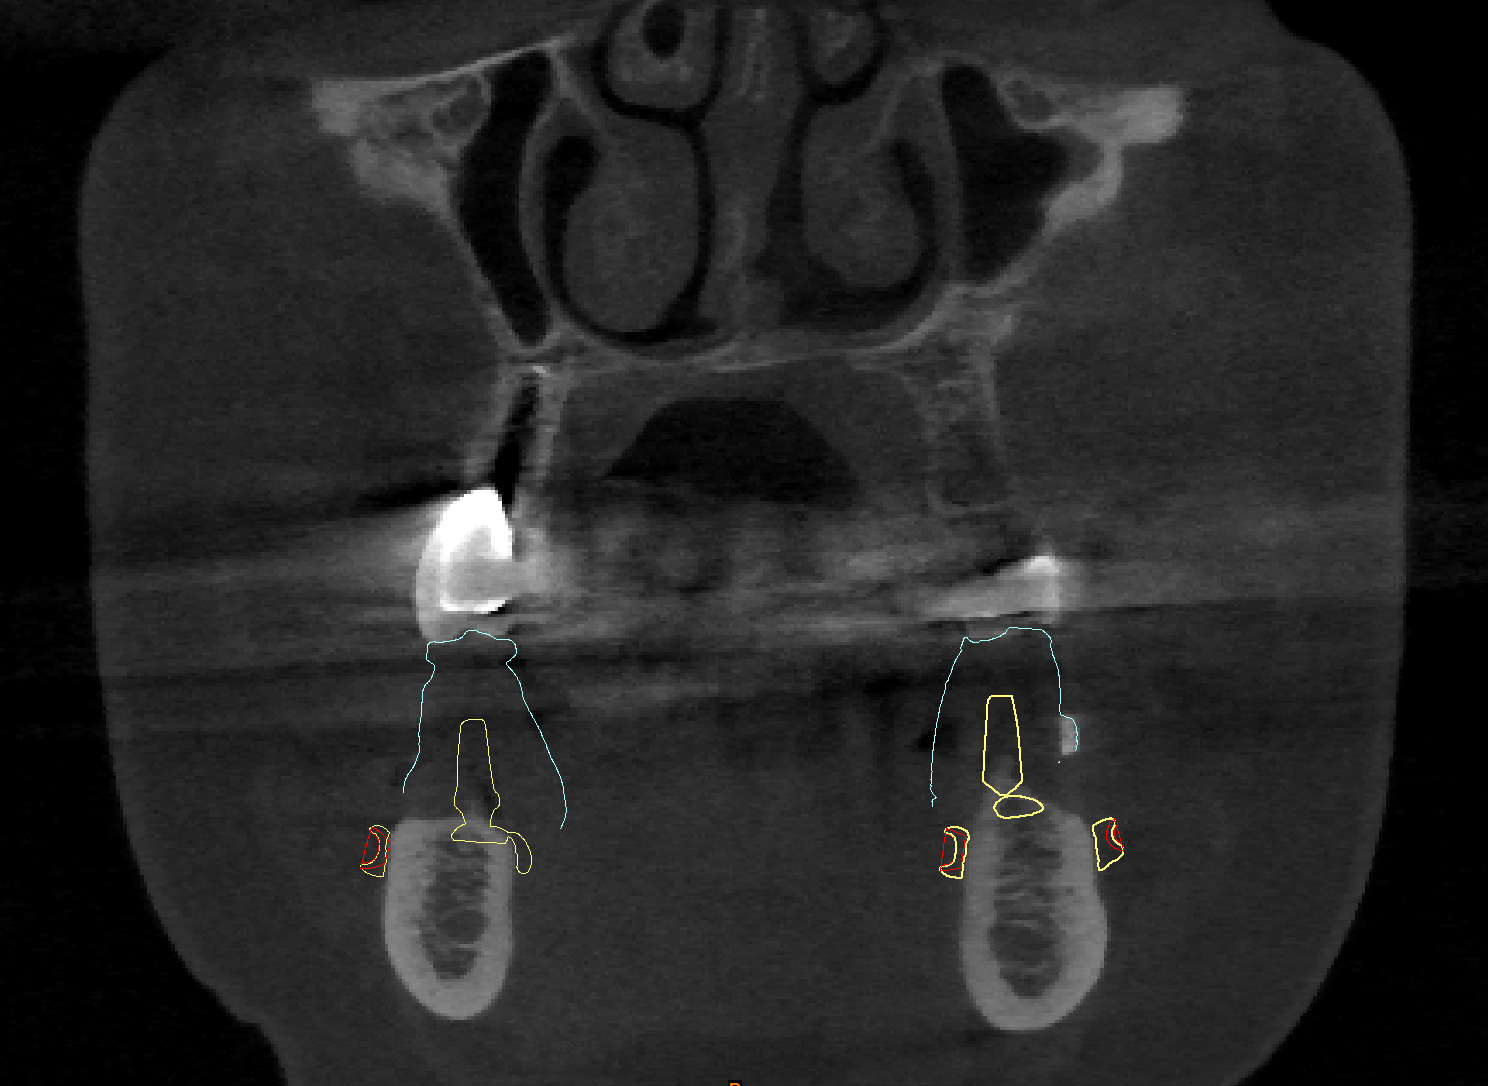

Vista coronale degli impianti in sezione.

Fig. 1. Vista coronale degli impianti in sezione.